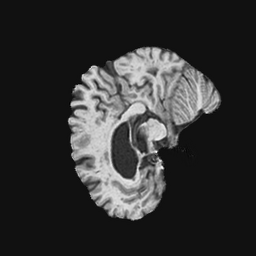

Exp. 3: Adult thorax data: To show the versatility of our approach we also apply it to adult thorax scans. For this experiment no organ specific training is performed but the whole volume is used. We evaluate reconstruction performance similar to Exp. 1 and prediction performance when is projected on an external plane, comparable to X-Ray examination using C-Arms. The latter provides insights about our method’s performance when applied to interventional settings in contrast to motion compensation problems. 60 healthy adult thorax scans were randomly selected, 51 scans used for and nine scans used for . Each scan is intensity normalised and resampled in a volume of with spacing . Using the Fibonacci sampling method, 25 sampling plane of size , evenly spaced between -50 and +50, were rotated over 500 normals. Training took approximately 20 hours for 60 epochs. Fig. 4c shows an example reconstruction result gaining 28dB PSNR with additional SVR. prediction takes approx. 20 ms/slice for this data.

0..5.3 Exp. 3:

We replicated the experiment on adult thorax data without specifically segmented organs. This approach was applied to CT acquisition, shown in Fig 13 and 14, as well as Digitally Reconstructed Radiographs generated using Siddon-Jacobs Ray Tracing shown in Fig. 16.